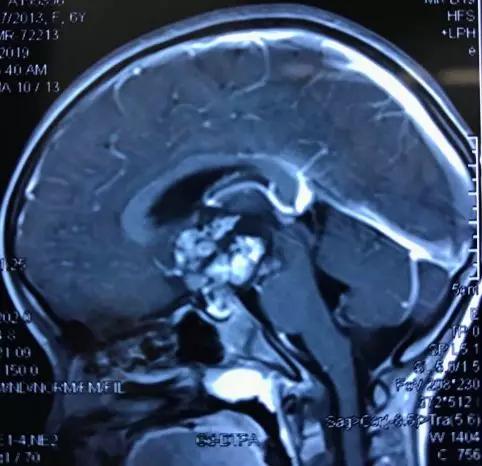

这是一例孟国路主任手术的患者。

6岁女孩左眼失明一个月,右眼挨近失明,就诊于宣武医院小儿神经外科中心,发现鞍区巨大畸胎瘤,经孟国路主任医师团队的紧迫救治,全切除肿瘤,术前失明的一侧视力重现光亮,右眼视力大幅度康复,病儿康复正常日子,肿瘤得到治好。

术前MRI